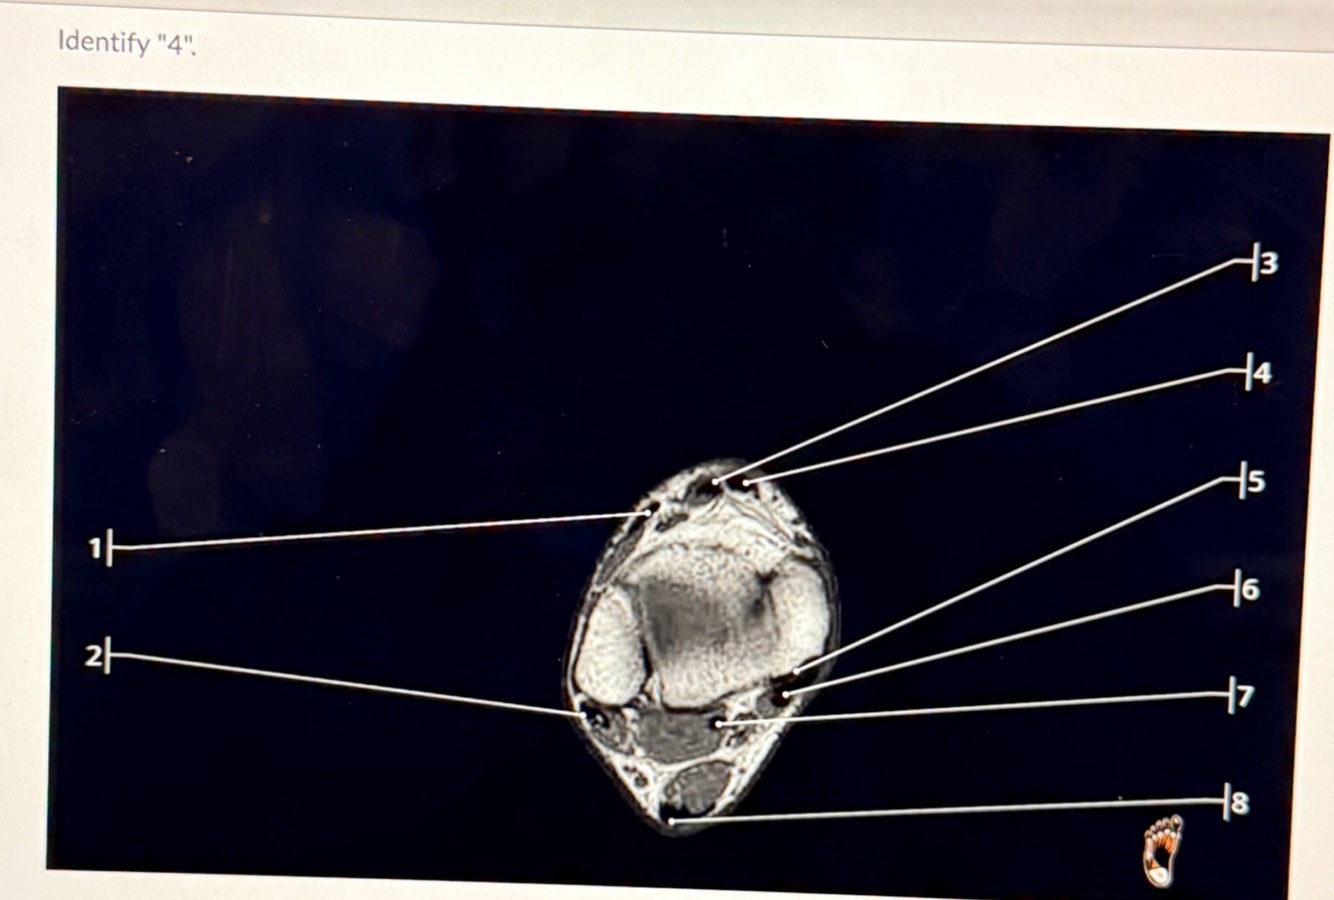

4

Q

A

Tibialis anterior tendon